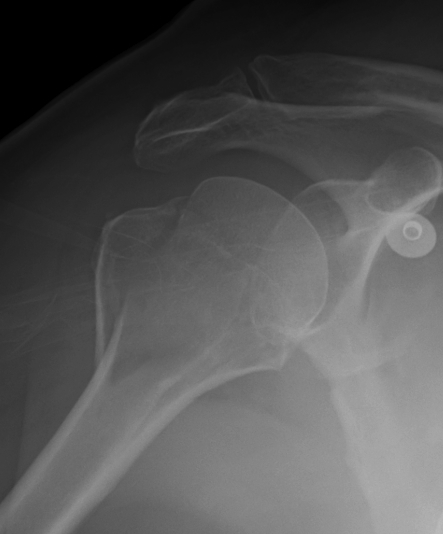

Xray

True AP

Scapular Lateral

Axillary Lateral

Garth (aim beam caudally)